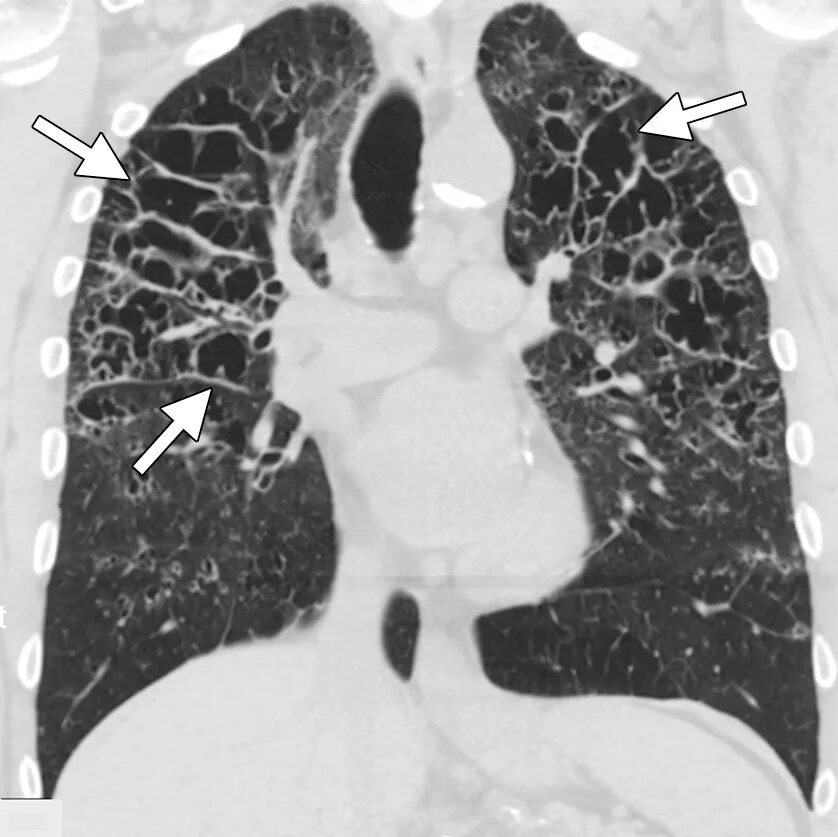

Кт х